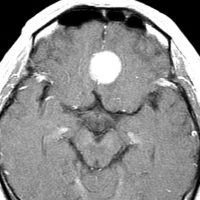

- MRI T1強調画像やT2強調像で,さまざまな信号を呈します(白っぽいことも灰色にみえることもあるということです)

- ガドリニウム造影剤で,髄膜腫がはっきりみえます(コントラストがついて白く見えます)

- T2強調やフレア画像では,腫瘍周囲に強い脳浮腫(脳が腫れる)があることも多いです

左は,造影剤を使ったガドリニウム増強MRIです。腫瘍が白く丸く見えます。右はフレア画像で,腫瘍の周囲の脳浮腫(脳のはれ)です。左前頭葉が,かなり強くはれています。この腫瘍は小さいのですが,脳のはれが強すぎるので手術摘出したほうがいいです。浮腫が悪化すると,てんかん発作や認知機能低下がでる可能性があります。